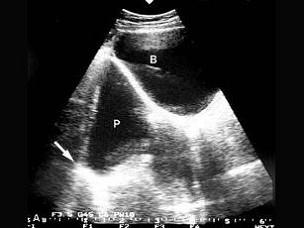

问题 下列声像图显示的是?(?)

选项 A.边缘声影 B.阻抗伪像 C.旁瓣效应 D.镜像伪像 E.散射伪像

答案 D